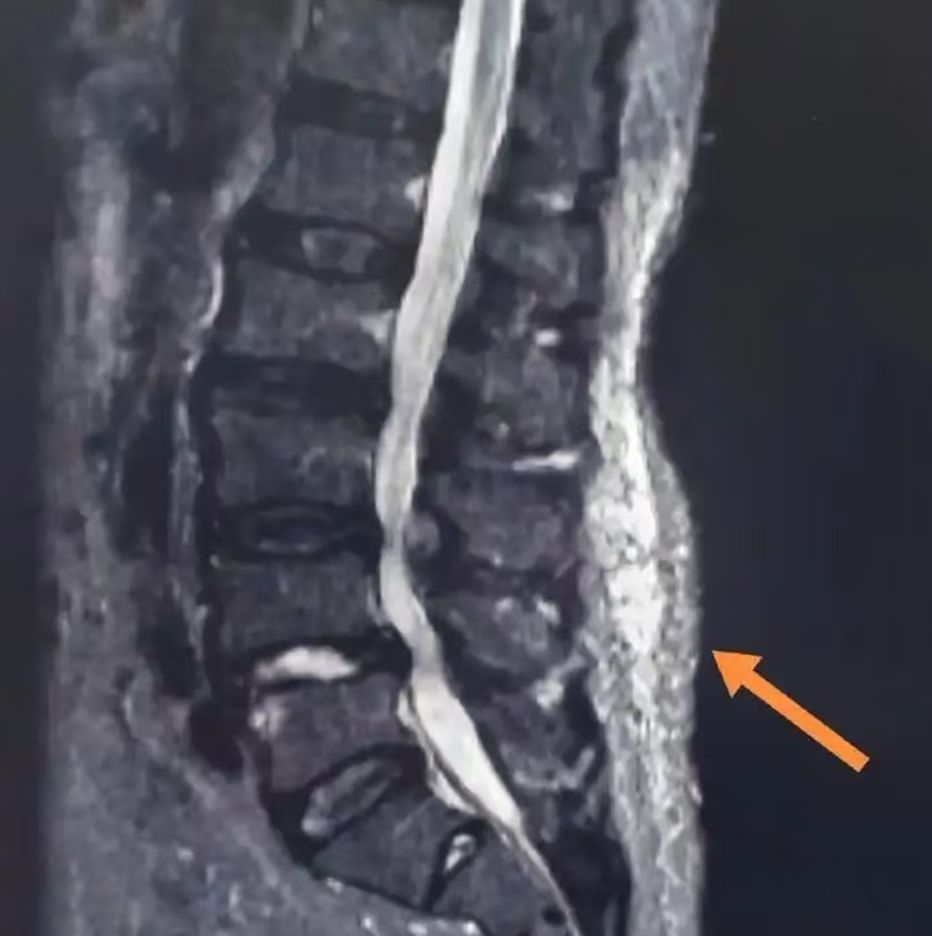

但是现在可先进多啦!还可以通过高频超声、MRI弹性成像这些“高科技雷达”,能把藏在里面的病灶照得一清二楚,误诊漏诊?勿可能的事!